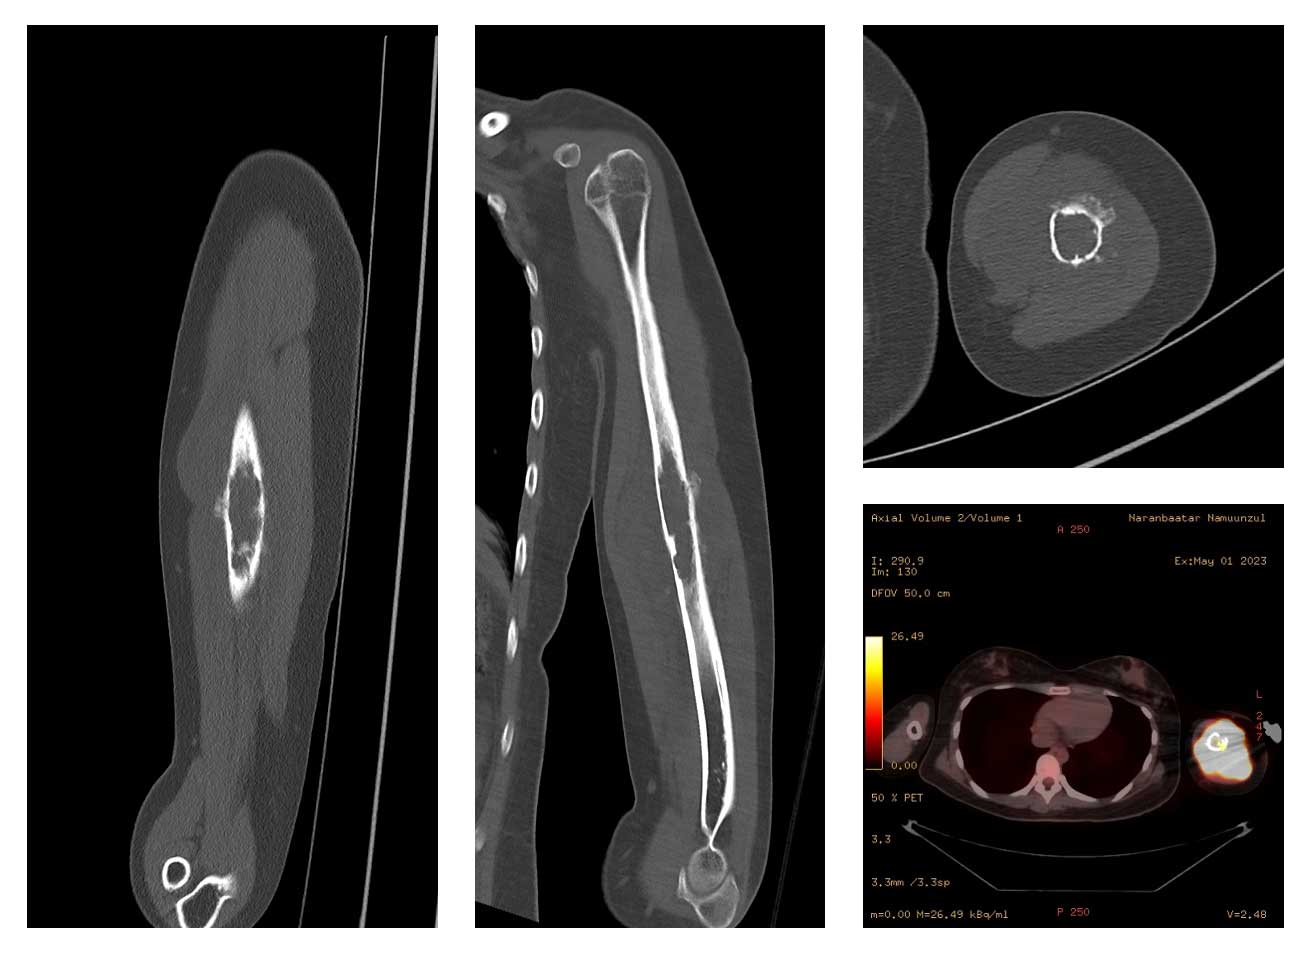

Ameliyat Öncesi: Tomografide ciddi yıkım, düzensizlik ve periost reaksiyonu, PET’de yoğun artmış aktivite görülmekte.